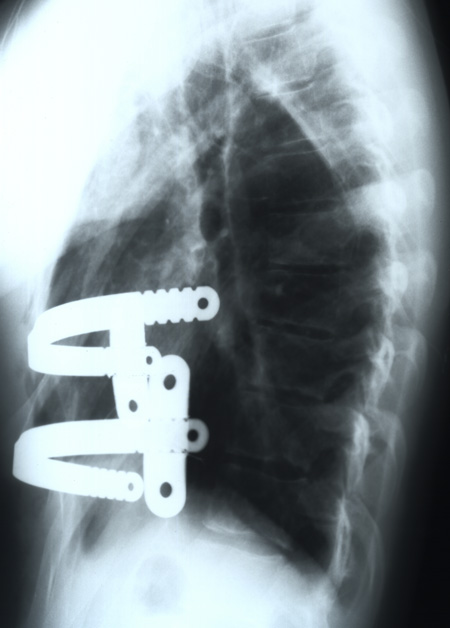

La cirugía abierta tipo Ravitch, que consiste en la resección de los cartílagos costales deformados y esternotomías a demanda para poner la pared torácica a plano, acompañada o no de la fijación con una férula metálica para darle estabilidad a la pared y reducir el dolor postoperatorio. Es una cirugía de larga duración, con resecciones costales y osteotomías, pérdidas sanguíneas y una cicatriz visible. La tendencia actual es a indicar  cada día menos este tipo de cirugías.

El otro procedimiento es la técnica minimamente invasiva de Nuss, que consiste en la introducción de una férula metálica por una pequeña incisión lateral del tórax, bajo visión toracoscópica. Esta barra se modela adecuadamente y levanta al girarla, la depresión del esternón y las costillas. Es una técnica muy bien aceptada por la comunidad quirúrgica, no precisa de resecciones óseas, y sólo deja dos pequeñas cicatrices en los laterales del tórax. Requiere un buen control del dolor postoperatorio. Normalmente es una cirugía muy bien tolerada por el paciente, exenta de complicaciones importantes y produce una gran satisfacción del niño y sus familiares, con unos resultados buenos, estables y definitivos. Esta barra debe permanecer in situ un mínimo de dos años, antes de proceder a su retirada.